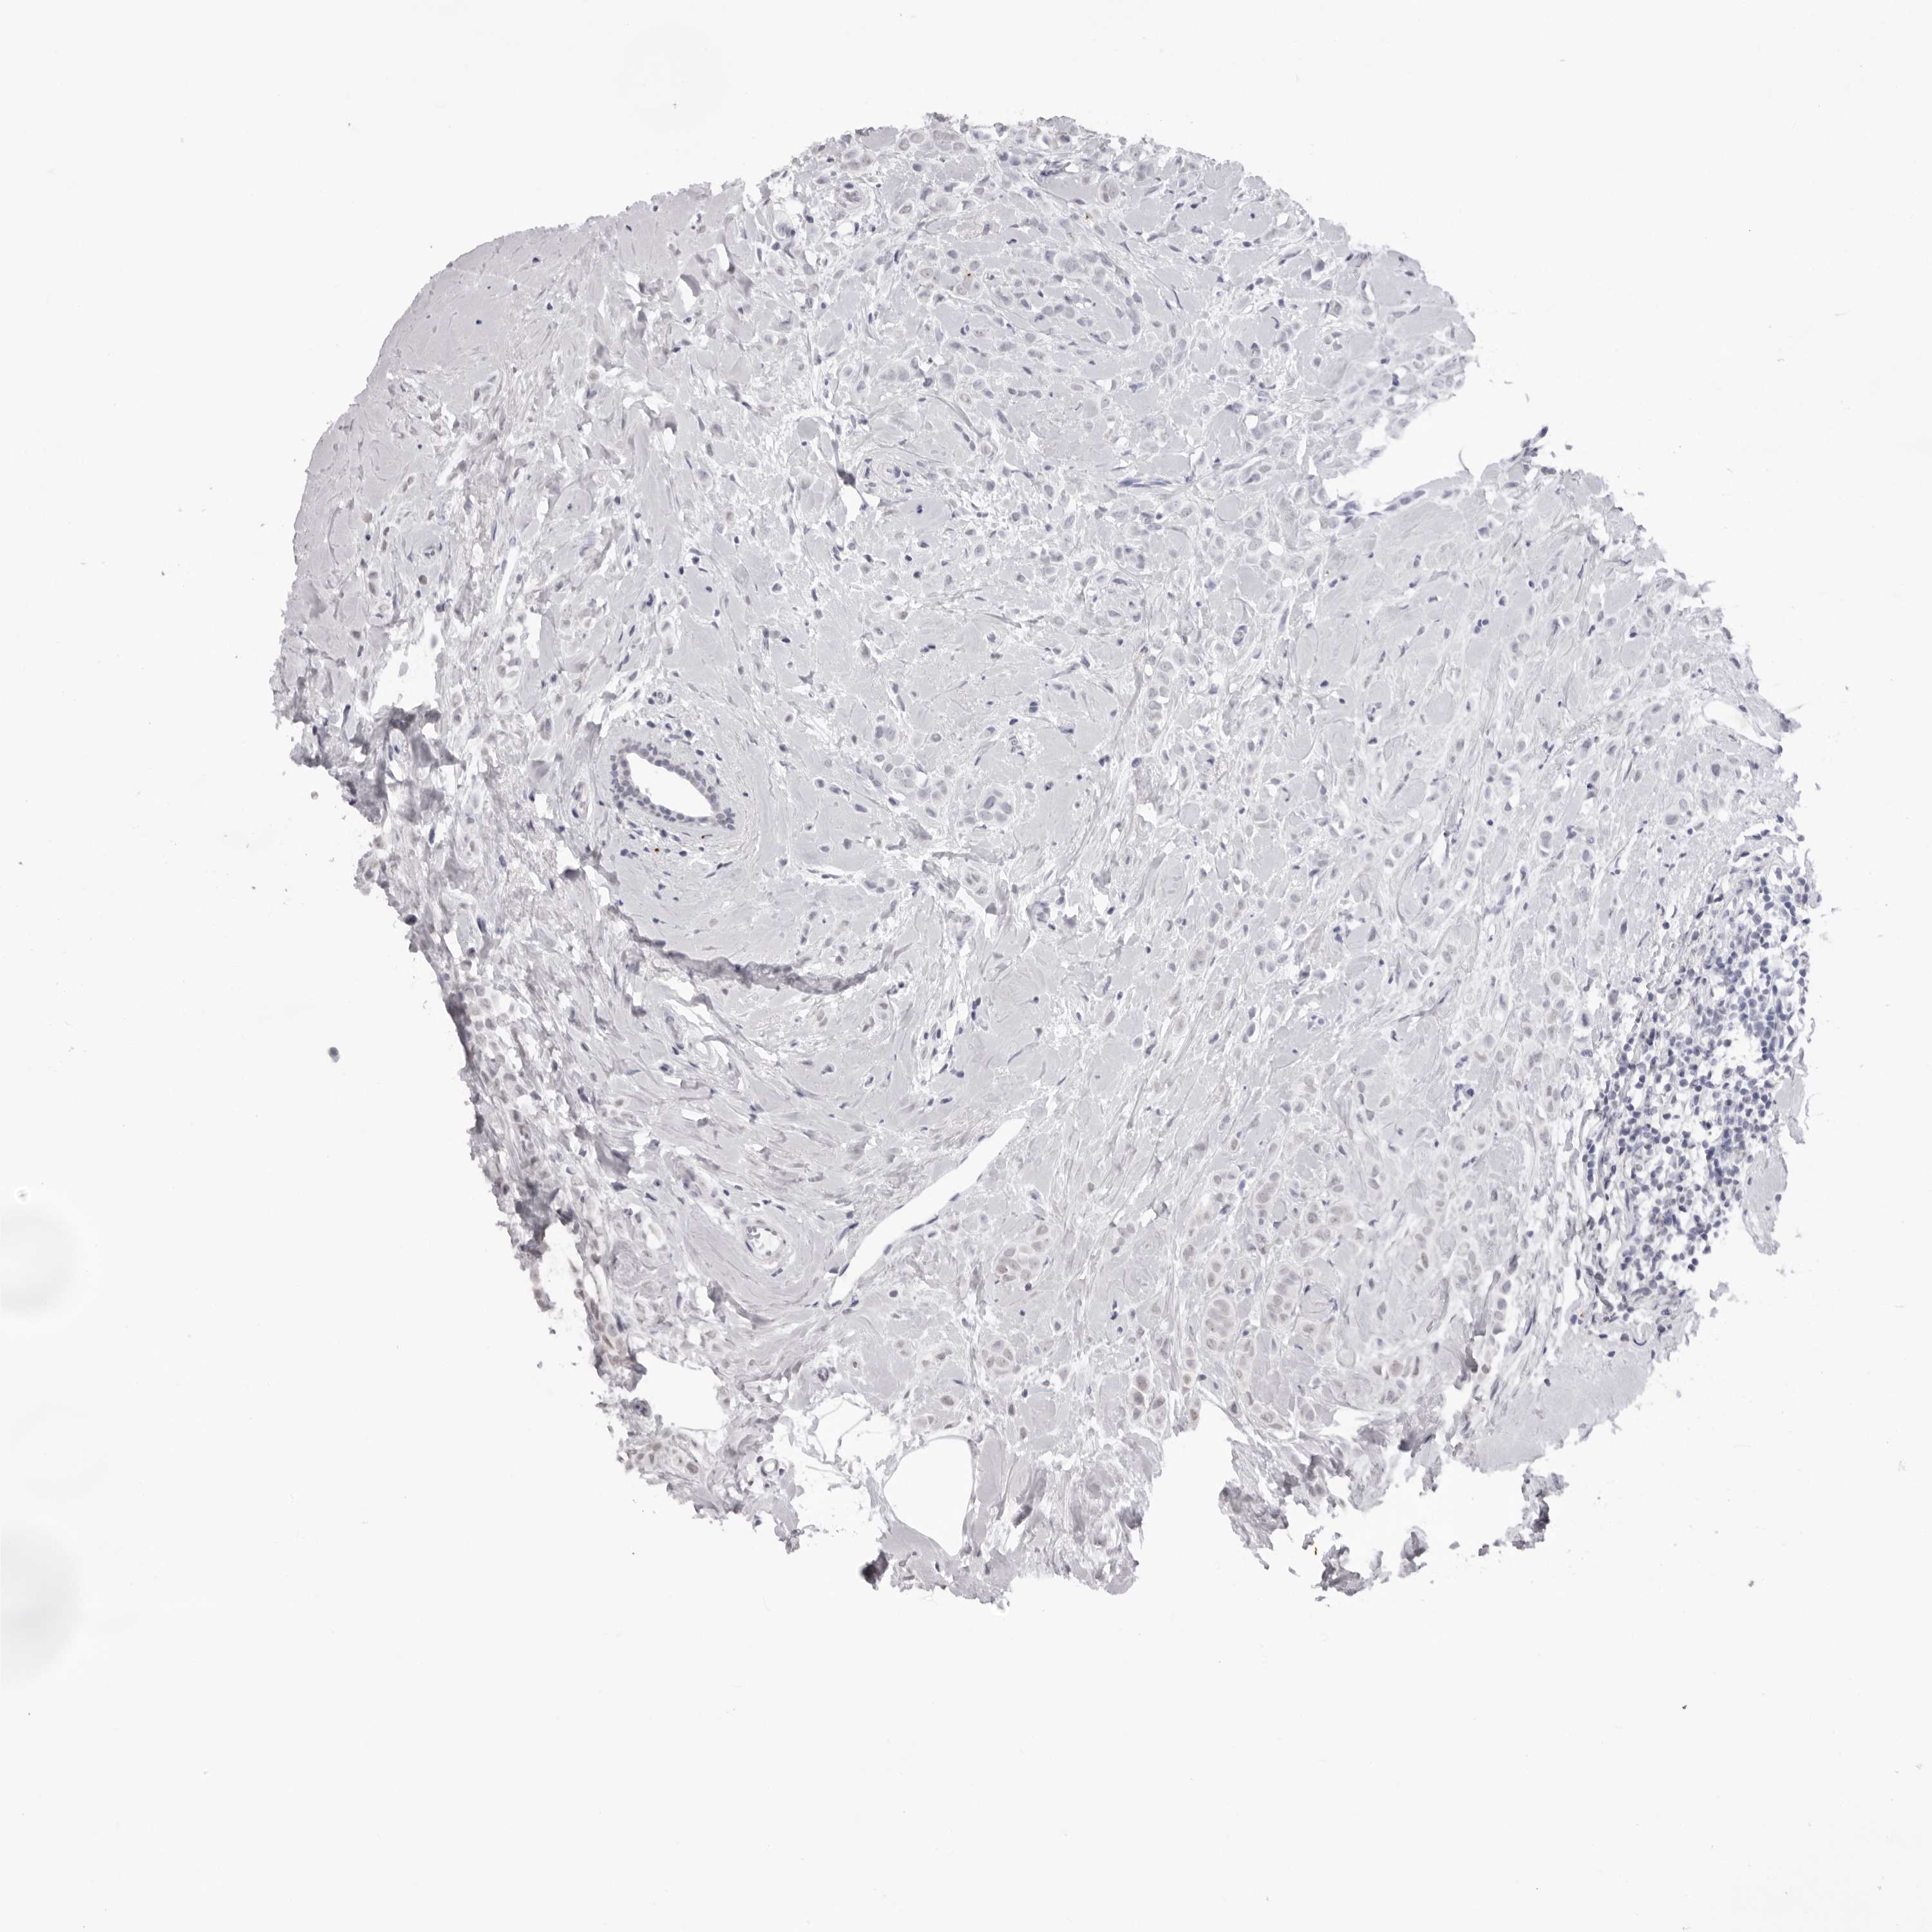

CANCER BREAST CANCER Show tissue menu

BRCA TCGA BRCA VALIDATION PROTEIN EXPRESSION

NTM is not prognostic in Breast Invasive Carcinoma (TCGA)

Average pTPM 10.8

Number of samples 1022